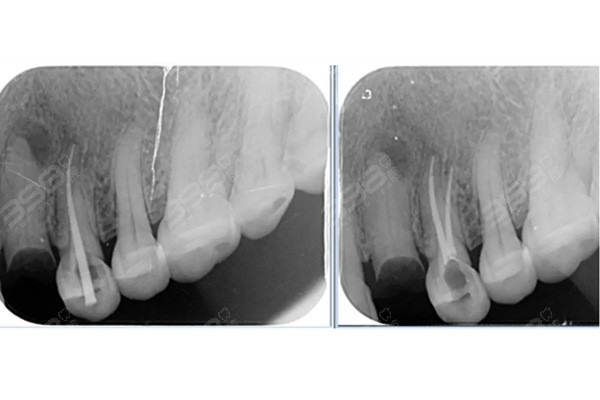

根管治療是一種通過清除牙齒內(nèi)部感染物質(zhì),對牙齒進行修復和恢復的方法,這種方法適用于牙髓炎、根尖周炎等牙齒疾病的治療,根管治療的主要目的是消除感染、防止再次感染,并恢復牙齒的正常功能。